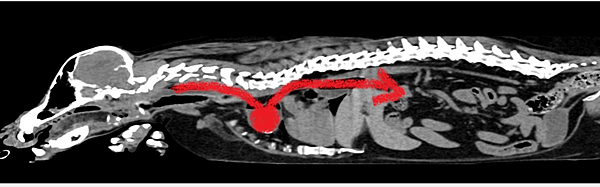

以往,我們醫院最多的病人排行榜依序是:臘腸,貴賓,瑪爾濟斯,法鬥跟柯基。

可是今年不知道怎麼回事,法鬥的數量急遽增加,這個禮拜癱掉的法鬥,竟然比臘腸還要多。